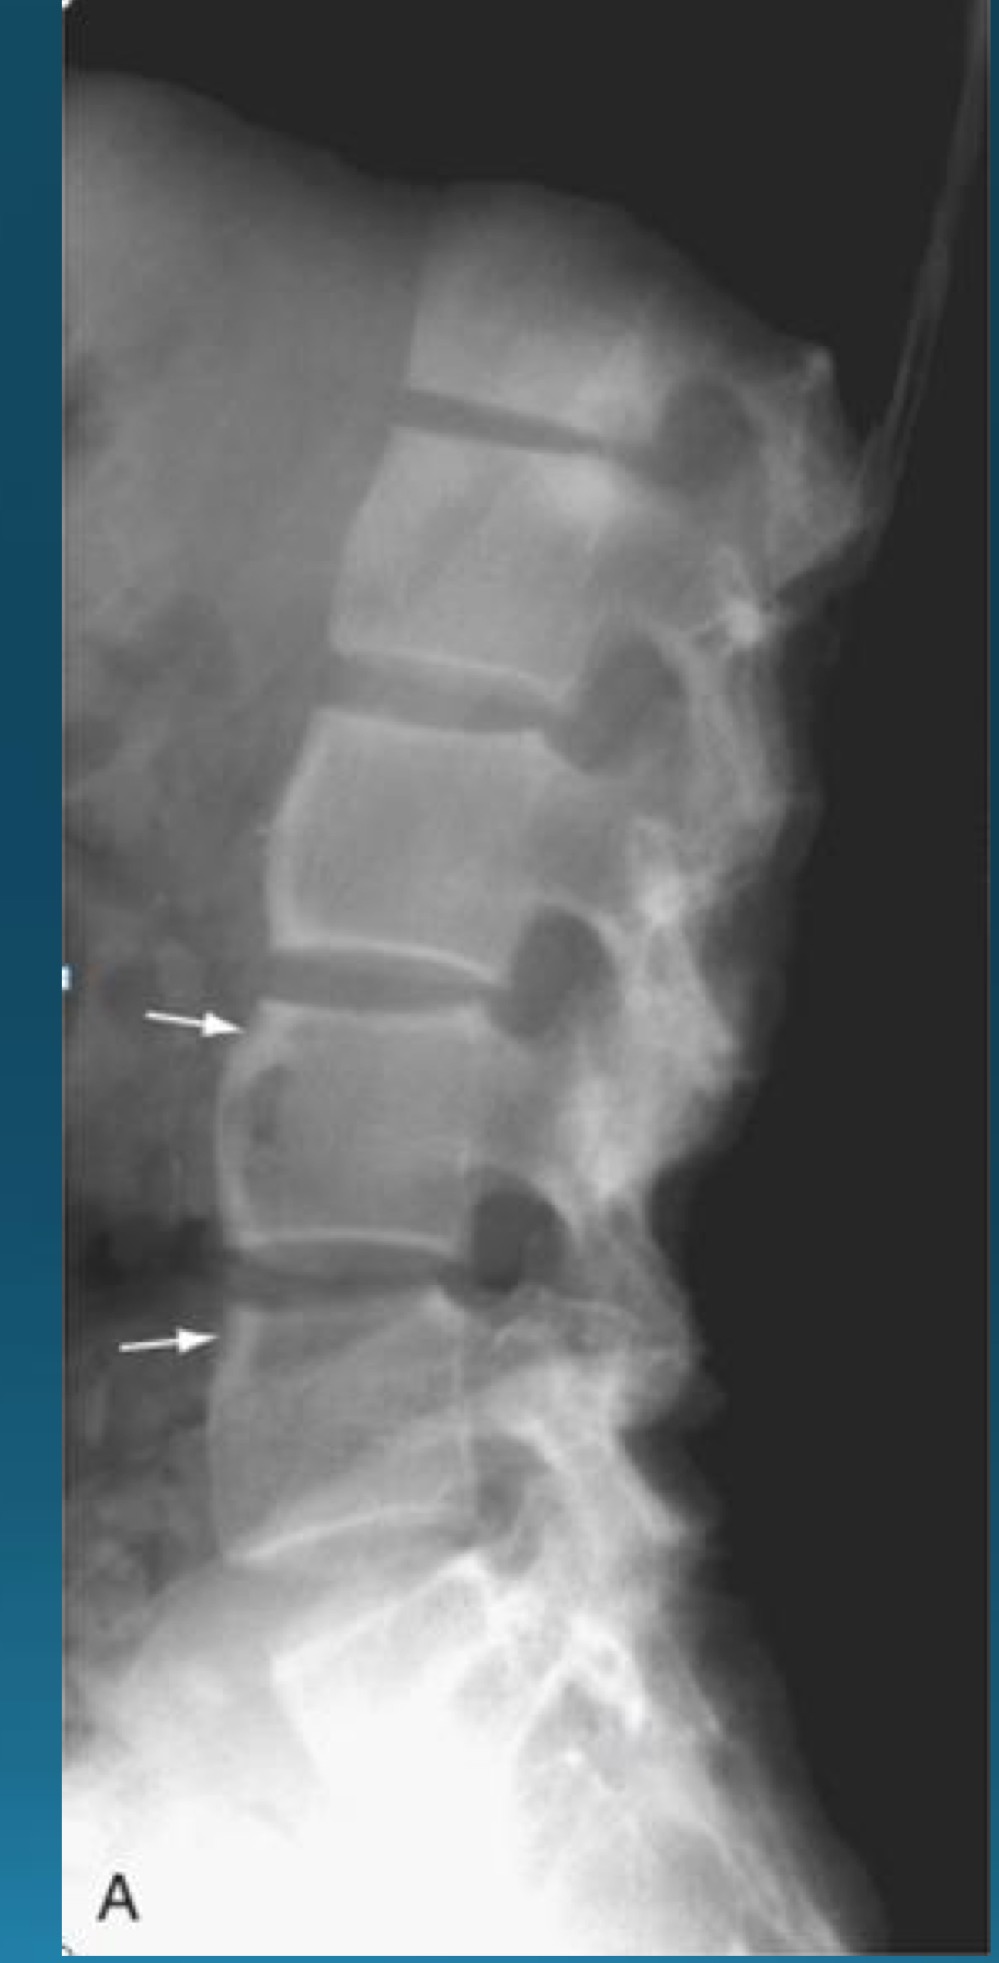

what are the signs seen in this image? what diagnosis would you make?

barrel shaped vertebra

AS